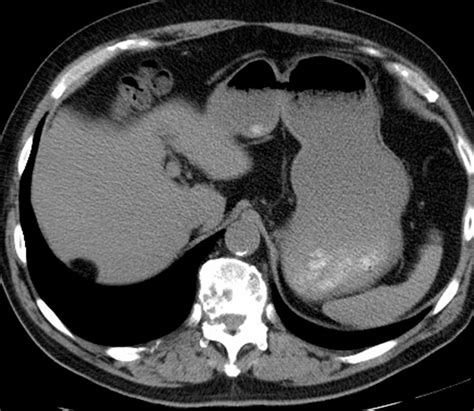

Imaging studies play a crucial role in the diagnosis and management of liver diseases. The Capsule of Glisson is often visualized on imaging studies, providing valuable information about the liver's anatomy and pathology. Ultrasound, CT, and MRI are commonly used imaging modalities for evaluating the liver and its capsule.

Ultrasound is a non-invasive and readily available imaging modality that can visualize the liver and its capsule. It is useful for detecting abnormalities such as cysts, tumors, and inflammation. However, ultrasound has limited sensitivity for detecting small lesions or subtle changes in the capsule.

CT and MRI provide more detailed images of the liver and its capsule, allowing for the detection of small lesions and subtle changes. These modalities are particularly useful for staging liver tumors, planning surgical procedures, and monitoring treatment response.

CT is a widely used imaging modality that provides detailed images of the liver and its capsule. It is particularly useful for detecting small lesions and subtle changes in the capsule. CT scans involve the use of X-rays and a computer to create cross-sectional images of the body.

During a CT scan, the patient lies on a table that slides into a circular opening. The CT scanner rotates around the body, emitting X-rays that are detected by sensors. The data is then processed by a computer to create detailed images of the liver and its capsule. Contrast agents, such as iodine-based dyes, may be administered to enhance the visibility of blood vessels and other structures.